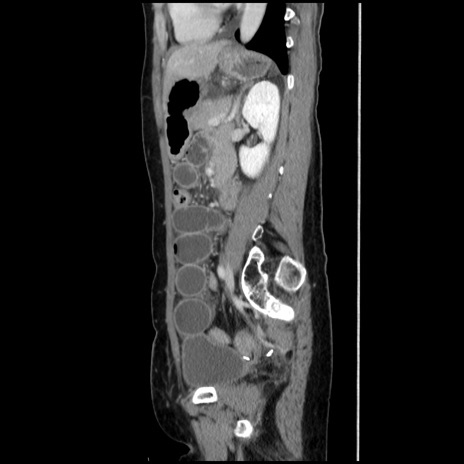

横断像

【症例】40歳代 女性

【主訴】上腹部痛、嘔気・嘔吐

【現病歴】約9時間前頃から急に上腹部痛、嘔気、嘔吐が出現。改善しないため救急要請。

【既往歴】子宮頚癌(広汎子宮全摘術、放射線療法)、腸閉塞

【身体所見】腹部:平坦、軟、腸雑音亢進、上腹部を中心に腹部全体に圧痛あり。

【データ】WBC 8400、CRP 0.03